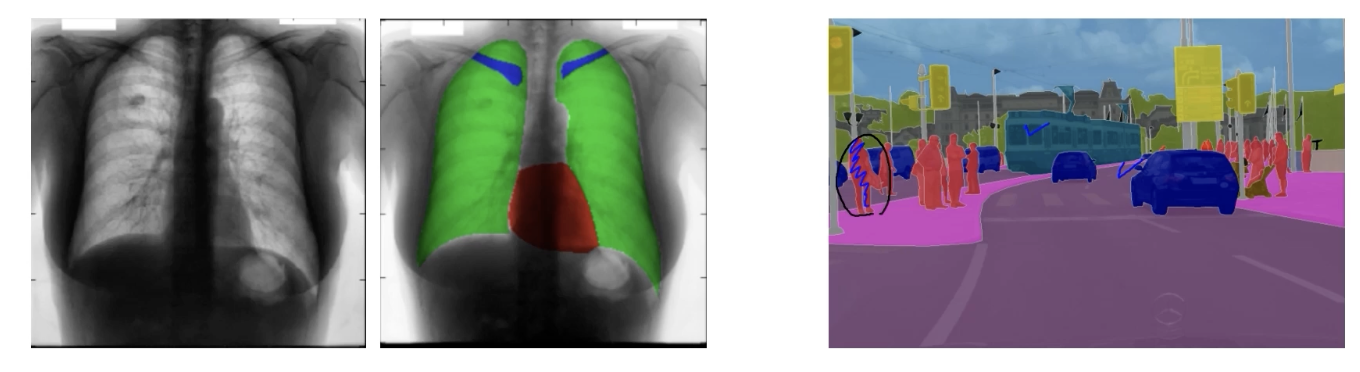

Semantice Segmantation

: Image classification 을 pixel 단위로 진행

영상 속에 있는 물체에 mask 생성

다만, 같은 클래스 서로 다른 물체가 겹쳐져 있을 때 구분 못한다.